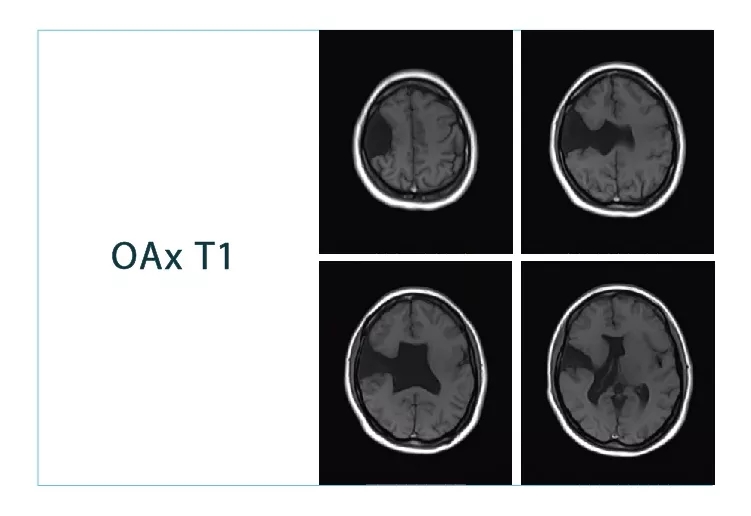

【朗润影像档案】20180824磁共振影像病例结果讨论